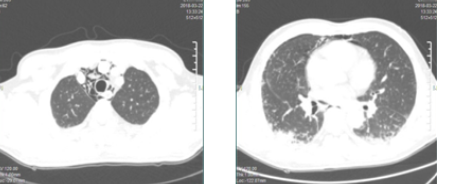

2018年3月22日,患者突然出现右侧颈根部皮下气肿,胸部CT平扫示颈根部及纵膈积气(见下图),双肺间质性肺炎,考虑病情加重,立即下达病危通知,持续氧疗,调整免疫抑制剂,同时护理团队加强护理治疗。